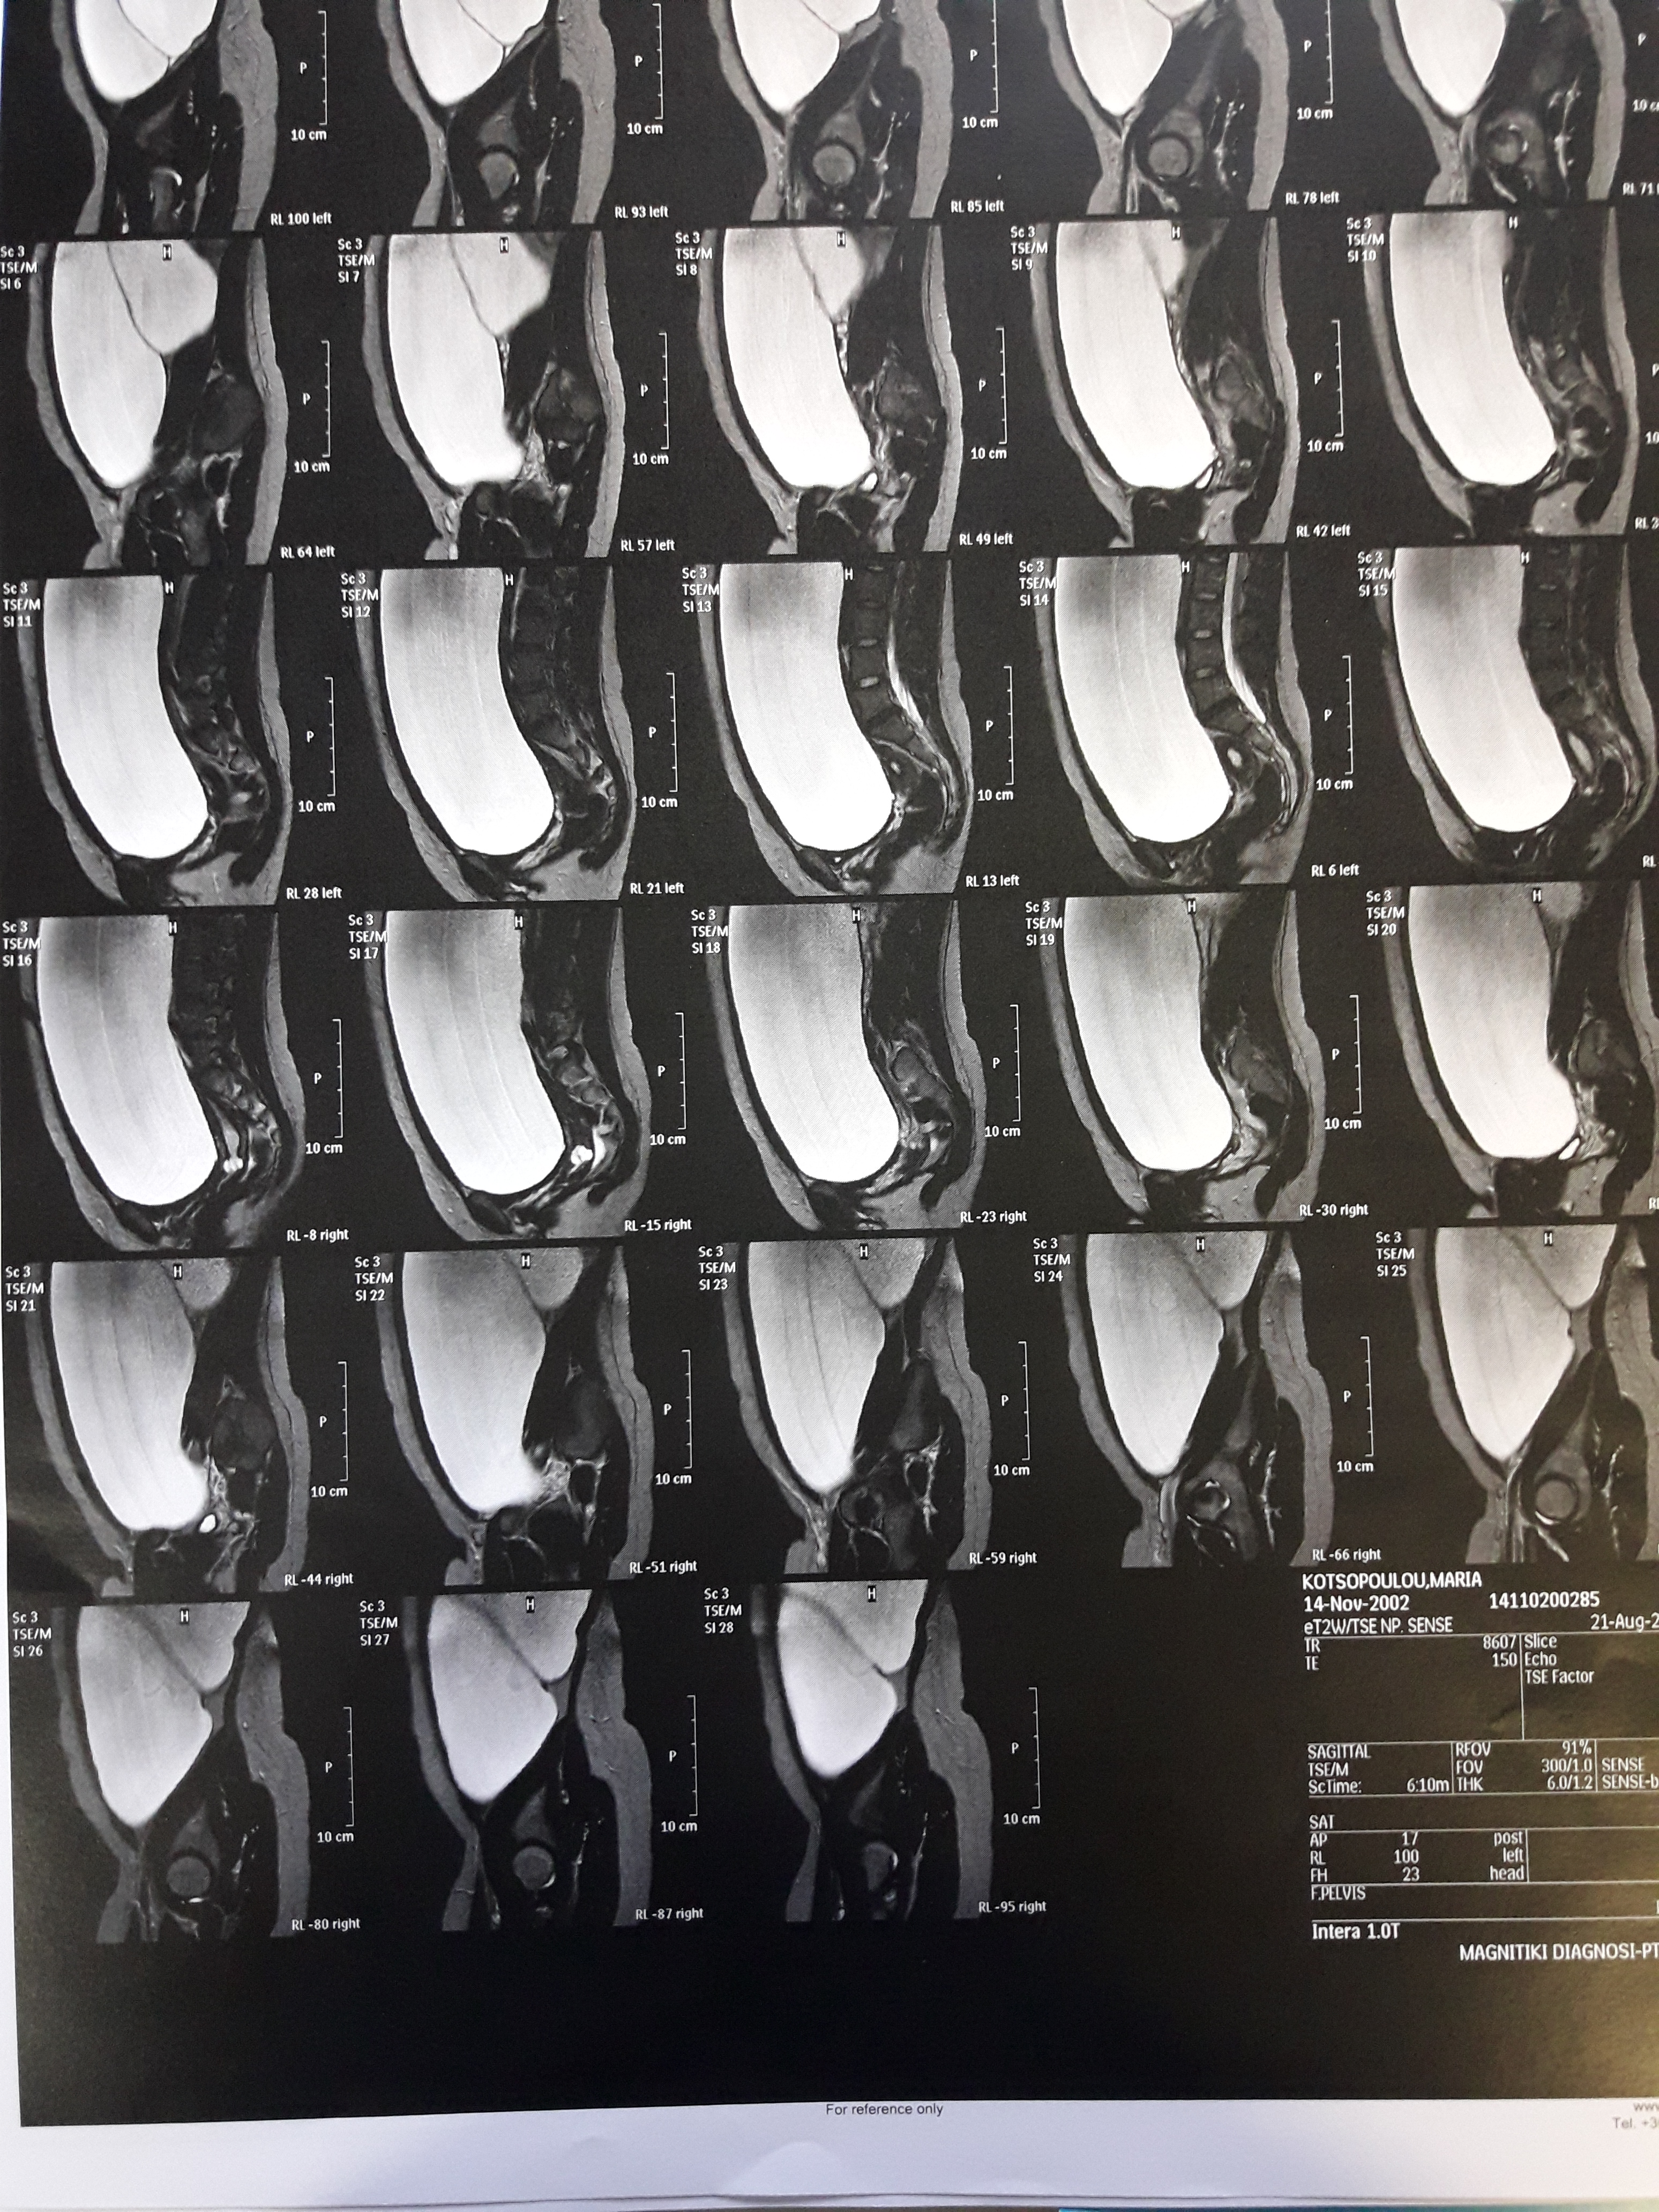

Largely distended abdomen thought to be secondary to dysmenorrhea is evident (Courtesy Dr. V. Penopoulos)